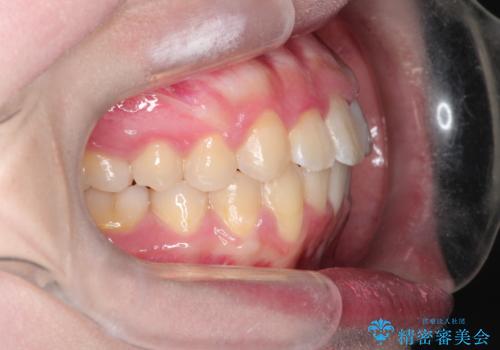

【インビザライン】前歯の凸凹を非抜歯で治療

- 前歯の凸凹を主訴の来院されました。

奥歯を後ろの方に移動させるために矯正用のアンカースクリューを使いながら治療をおこないました。

患者さんの都合により、マウスピースの装着時間が不足したため、途中からワイヤーにて治療を行いました。